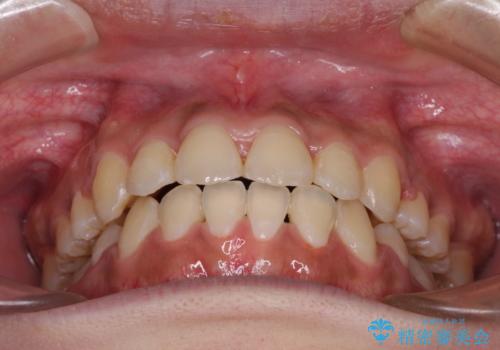

- 八重歯と上下前歯のでこぼこを気にして来院された患者様です。

上下前歯部叢生のスペース獲得のため、上下顎左右小臼歯各1歯(計4本)と全ての親知らずを抜歯して、矯正治療を行うこととしました。

上下の正中位置が大きくずれていたため、治療期間の長期化や正中が合わないまま終了することが予想されましたが、思っていた以上にスムーズに歯が移動し、満足いただける仕上がりとなりました。